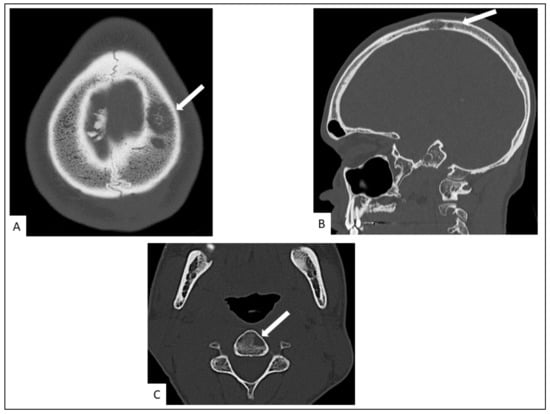

5.4. Musculo-Skeletal KS